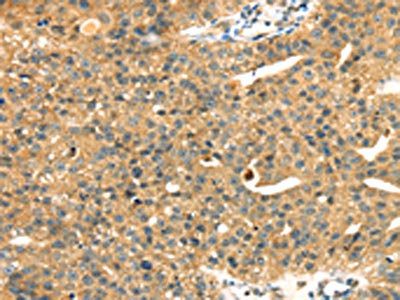

The image on the left is immunohistochemistry of paraffin-embedded Human liver cancer tissue using CSB-PA644665(MAPK12 Antibody) at dilution 1/25, on the right is treated with fusion protein. (Original magnification: ×200)

The image on the left is immunohistochemistry of paraffin-embedded Human breast cancer tissue using CSB-PA644665(MAPK12 Antibody) at dilution 1/25, on the right is treated with fusion protein. (Original magnification: ×200)